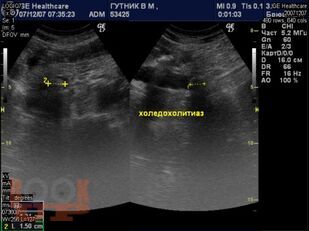

Учебно-методическое пособие посвящено актуальным проблемам этиологии, патогенеза, диагностики, современным методам консервативного и оперативного лечения механической желтухи. Представлены новые классификации, схемы консервативного лечения, современные виды оперативного лечения, учитывая утвержденные клинические рекомендации Российского общества хирургов (2018 г.). Издание иллюстрировано рисунками, таблицами, имеются тестовые задания и задачи. Пособие предназначено для слушателей дополнительного профессионального образования и ординаторов, обучающихся по специальности 31.08.67 Хирургия.